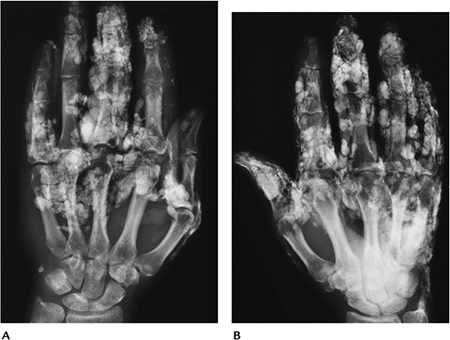

![]() |

FIGURE 13-20 Mixed connective tissue disease. (A,B) Radiographs of both hands showing juxta-articular osteopenia and extensive soft tissue calcifications.